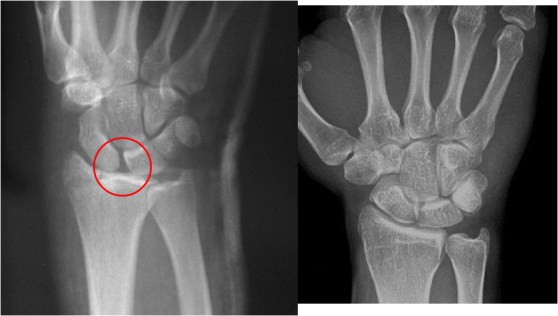

SIGNO DE LA BANDA DEL ESCAFOIDES

La banda adiposa del escafoides es una imagen lineal o triangular de densidad grasa, que se localiza entre el escafoides y las vainas tendinosas del abductor largo y del extensor corto del pulgar. El borramiento o desplazamiento de esta línea se presenta en las fracturas del escafoides, de la apófisis estiloides radial o de la base del primer metacarpiano, aun cuando no se vea la línea de fractura. En el ejemplo puede verse el borramiento de la banda adiposa del escafoides y la fractura de este hueso.

La flecha marca la banda adiposa del escafoides en una radiografía normal.